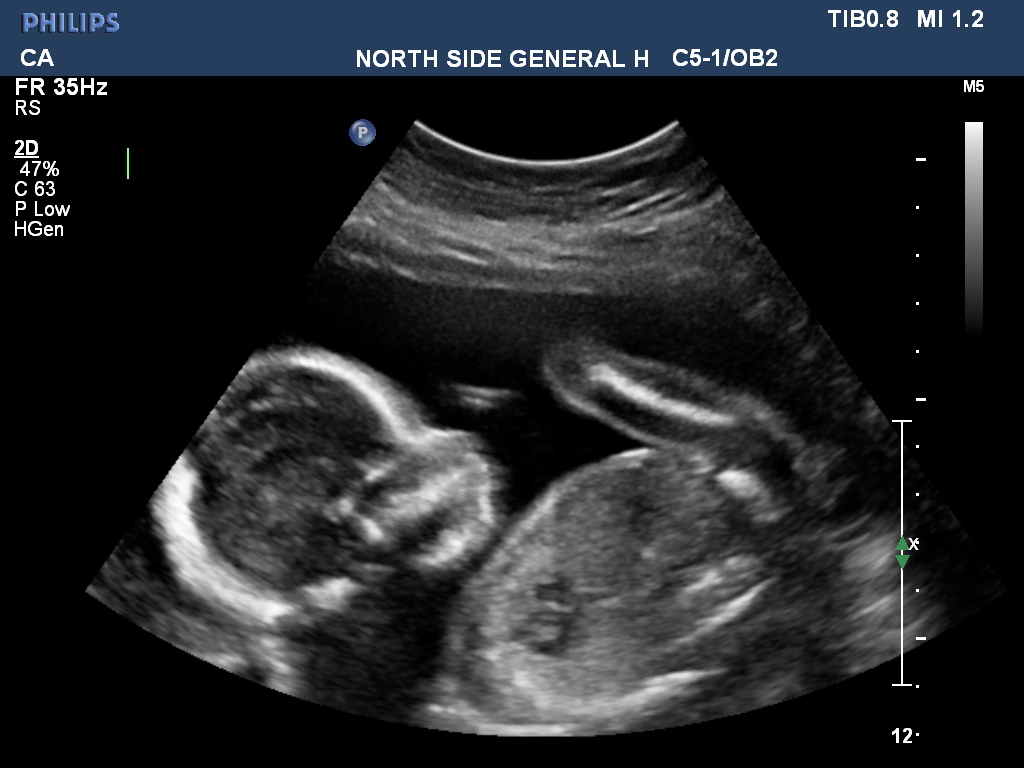

Just for fun because I don't think there are any clues here. And not sure what I'm looking at in #3 :lol: I didn't ask the tech b/c I want to be surprised since this is our last but guessing is fun :) ETA - This is from today 20 weeks 5 days.

Attachment 39424

The last pic looks like little arms and tummy. So cute!